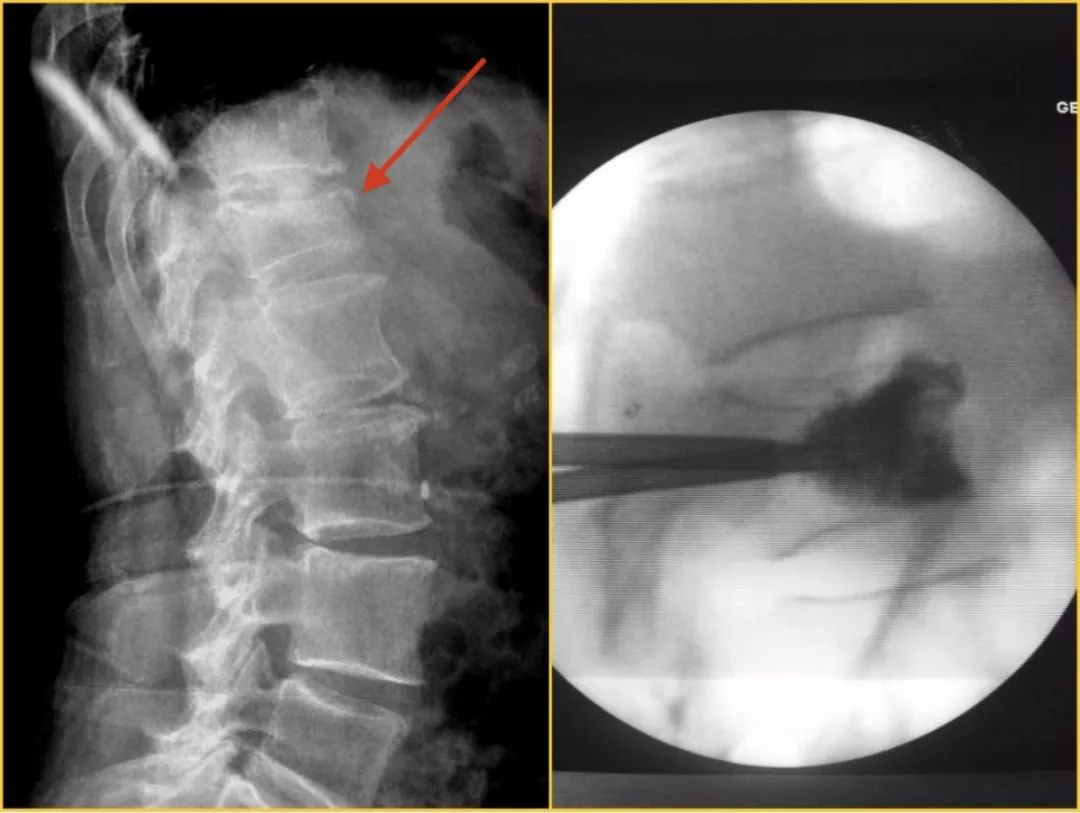

随着我国人口老龄化的加速,骨质疏松症作为中老年人最为常见的代谢性骨病,其所引起的胸腰椎压缩性骨折的发病率逐渐增加,且女性发病率显著高于男性,已经严重威胁着老年人的健康。